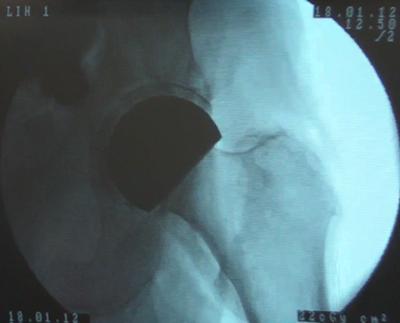

X-Ray of the Implant System in a Trial Cadaver Surgery

Cadaver Trial Surgery